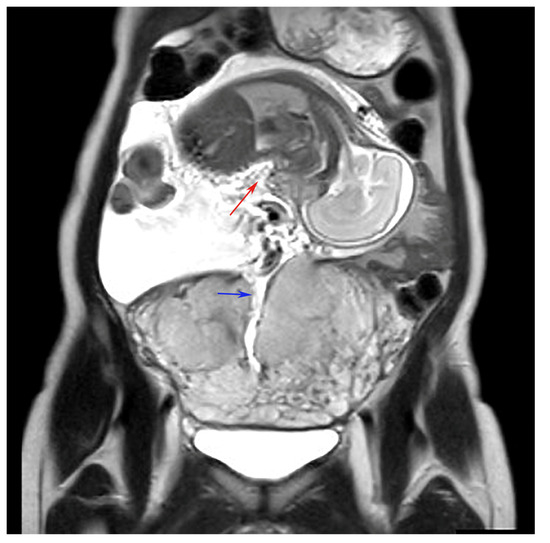

Fetus in the Abdominal Cavity After Uterine Rupture in a Primigravida Post-Adenomyosis Enucleation

Kamata, S.; Ando, H.; Matsuda, E.; Aoki, A.; Komatsu, A.; Kawana, K. Fetus in the Abdominal Cavity After Uterine Rupture in a Primigravida Post-Adenomyosis Enucleation. Diagnostics 2024, 14, 2470. https://doi.org/10.3390/diagnostics14222470